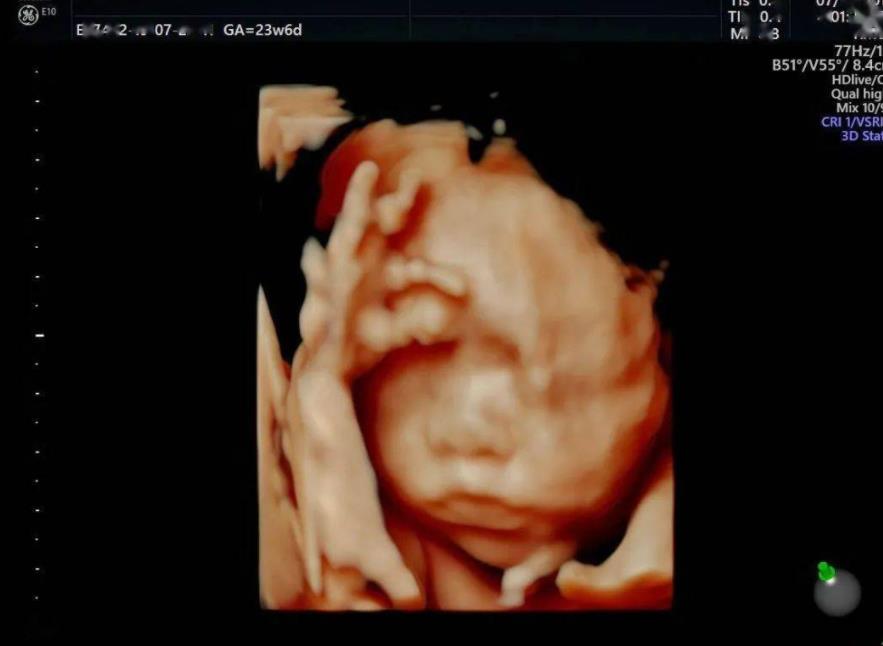

四維彩超是一種超聲技術,利用這種技術能夠監測到胎兒在肚子的發育情況,還能夠觀察胎兒的面部以及四肢,在懷孕期間,四維彩超主要是用來排畸的一項檢查,但是現在也有人認為,通過孕期四維檢查的結果,是能夠看出胎兒的性別的,如果說想要知道胎兒是男是女,...

四維判斷不了胎兒的性別。四維單上判斷胎兒是男孩的3個亮點分別為彩超影象、孕囊形狀以及雙頂徑和股骨長。四維是超聲檢查的一種,除了一般彩超的功能外,還可以進行胎兒頭面部立體成像,可清晰地顯示眼、鼻、口、下頷等狀態,可協助醫生直接對胎兒先天畸形進...

女性在懷孕期間的時候需要定期去醫院進行產檢,比如b超檢查、nt檢查、四維彩超檢查等等,以此可以瞭解腹中胎兒的發育情況,不過除了關注寶寶健康,不少孕媽也想通過各種跡象來推測懷的男孩女孩,其中通過四維彩超檢查的影象可以看出男孩女孩,如果胎兒雙腿...

四維彩超也是一種超聲技術,在懷孕期間主要是通過這項檢查,判斷胎兒是否存在畸形的情況,四維檢查能夠看到胎兒的面部和四肢,從而推斷是否存在缺陷,但現在也有不少人認為,通過四維檢查能夠判斷出胎兒的性別,因為四維檢查報告單上的資料很多,有的人認為能...